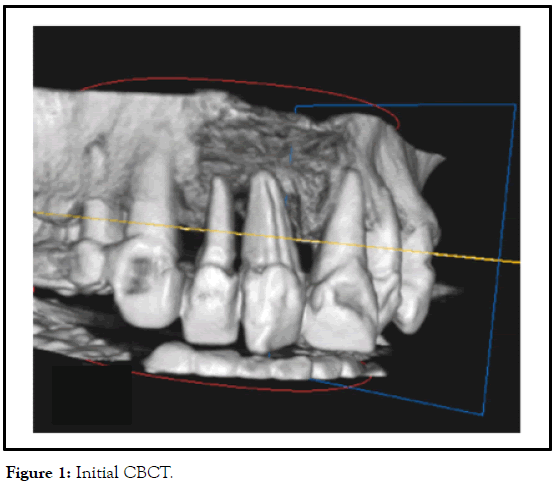

The replacement of two periodontal involved teeth (right central and lateral incisors/maxilla). Gingival crevices measured more than 10 mm, and the intraoral X-ray revealed complete absence of bone. CBCT affirmed the absence of alveolar bone, but revealed bone 4 mm-5 mm under the nose, and the disappointing periodontal condition of left central incisor (Figure 1).